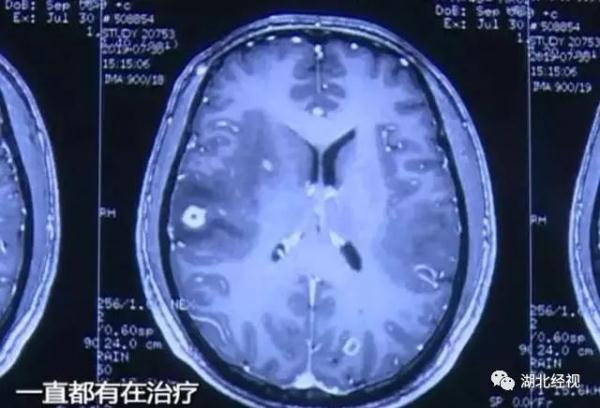

韦先生告诉我们,他去当地医院检查后被告知为“脑囊虫病”

据韦先生的主治医生介绍,韦先生经过一系列检查发现,他脑子里有很多虫子爬过的痕迹,被确诊为“脑囊虫病”。脑囊虫?那韦先生的癫痫跟这些虫子有什么关系?

医生表示,由于那些虫子在脑里死亡,引起了炎症和脑水肿需要将癫痫的致痫灶切除,因为韦先生的情况比较严重,经过详细诊断之后,医生决定马上为他做手术。在医生的手术之后,韦先生正在顺利康复中,也没有出现抽搐的情况了。不过对于韦先生,脑里那些虫子的出处,我们都深感意外。这一切竟然和韦先生家乡过年的一个习俗有关。

医生表示,在这些猪血里面最常见的就是猪肉绦虫,因为猪血没有煮熟,所以就会产生寄生虫的虫卵,损伤人体的大脑部位。